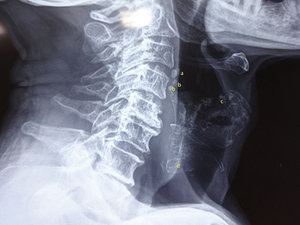

Fig. 2: Laryngeal cartilage calcifications: a) Triticeous, b) Superior cornua, c) Thyroid and d) Cricoid.

The pattern and rate of calcification / ossification can vary among individuals and are unpredictable. They can appear in unexpected and disordered patterns as well. Calcification becomes denser in appearance as age advances. Knowledge of the anatomical location and pattern of cartilage calcification is helpful when determining whether there is a foreign body or calcification in the thyroid gland. The thyroid cartilage is seen at the level C3-C5 and C6 for cricoid. (Fig. 2) The thyroid gland sits at the C5 level and extends inferiorly to the T1 level in some people.

Thyroid cartilage calcification / ossification starts by 20-25 years of age at the postero-inferior part of the lamina and inferior cornua. It then progresses upward and anteriorly. So, it is unusual to see isolated superior lamina or superior cornua ossification. Eventually, male thyroid cartilage completely ossifies, whereas in females the anterior aspect is left unossified. The thyroid cartilage calcification/ossification is used in forensics to determine the age of a person when other anatomical structures are missing.

Cricoid and arytenoid cartilages calcify in the third decade, but somewhat later than thyroid cartilage. The superior margin and lamina of the cricoid ossify earlier than other parts. Ossification of the cricoid can be identified even in the presence of thyroid cartilage ossification. Arytenoid calcification starts from the base of arytenoids sitting on the upper aspect of the cricoid lamina. When completely calcified, it has an L-shaped appearance.

Triticeous cartilages are variable. When present and calcified, they can be seen along the line between superior cornua of the thyroid and the posterior part of the greater cornua of the hyoid.